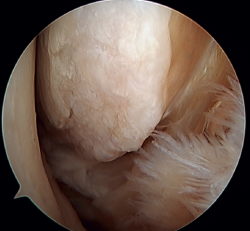

Tratamiento artroscópico de la inestabilidad rotacional/multidireccional

La inestabilidad rotacional es un concepto relativamente novedoso descrito en 2011 por Buchhorn(67), donde se describen lesiones combinadas del complejo lateral y del ligamento deltoideo, y una técnica de reconstrucción anatómica para ambas lesiones. Aunque no existe evidencia biomecánica de por qué se produce la lesión medial en pacientes que no han sufrido traumatismos en eversión, probablemente el estrés mantenido sobre el complejo medial en la inestabilidad lateral puede evolucionar a una inestabilidad rotacional, lo cual va en línea con la teoría del efecto dominó previamente explicada(5,62). Se estima que hasta el 10-15% de las ICLT pueden evolucionar a la lesión del complejo medial, afectando especialmente sus fibras más anteriores. Recientemente, Vega(68) describe la combinación de lesiones del complejo lateral con la lesión en “hoja de libro” (Figura 7) del fascículo tibiotalar superficial del ligamento deltoideo debido a la excesiva rotación interna en la inestabilidad lateral crónica, así como su tratamiento mediante reparación directa de ambas lesiones. Acevedo(34) y Vega(68) también describen la posición de seguridad de los anclajes en el maléolo medial.